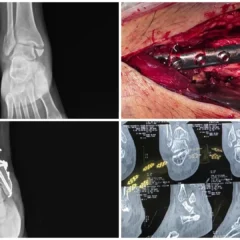

Clinical examination and imaging studies confirmed a Right Proximal Tibia Fracture involving both medial and lateral columns of the bone. Such fractures require precise anatomical reduction to restore joint alignment and maintain knee stability.

Open Reduction and Internal Fixation (ORIF) with Bicolumnar Plates and Screws

Mrs. Ananthamma underwent Open Reduction and Internal Fixation (ORIF) using bicolumnar plates and screws.